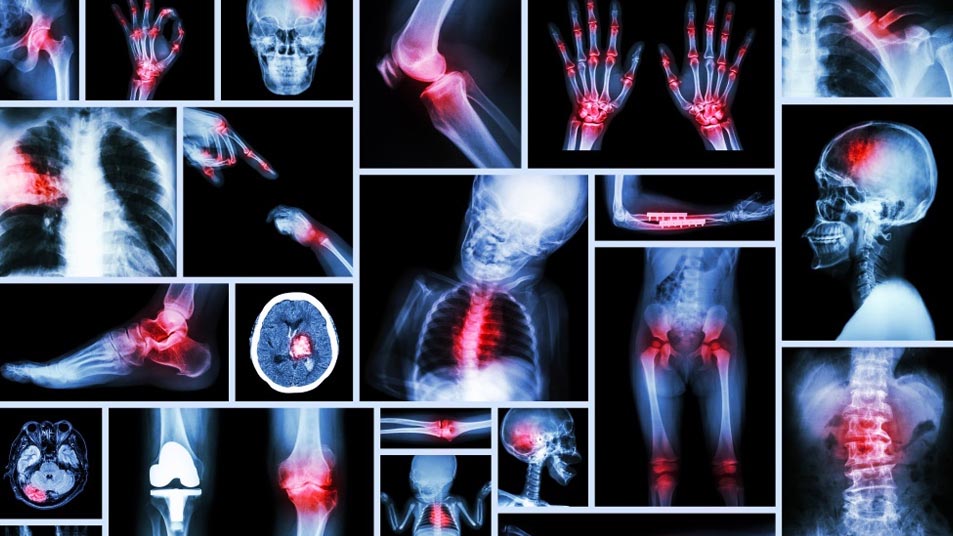

Diagnosing sciatica involves a combination of a physical examination and imaging tests. Doctors may perform tests to assess muscle strength and reflexes. Imaging tests, such as X-rays, MRI, or CT scans, can help identify the underlying cause of nerve compression, such as a herniated disc or spinal stenosis.

Diagnosing compressive myelopathy involves a combination of clinical evaluation and imaging studies. A thorough neurological examination can identify deficits and help localize the level of compression. Imaging studies, particularly magnetic resonance imaging (MRI), are crucial in visualizing the spinal cord, identifying the source of compression, and assessing its severity. Computed tomography (CT) scans and X-rays may also be used to evaluate bony structures and traumatic injuries.

Diagnosis of osteoporotic spine fractures typically involves a combination of clinical evaluation and imaging studies. X-rays are commonly used to identify vertebral compression fractures, while bone density tests, such as dual-energy X-ray absorptiometry (DEXA), are used to assess the severity of osteoporosis.